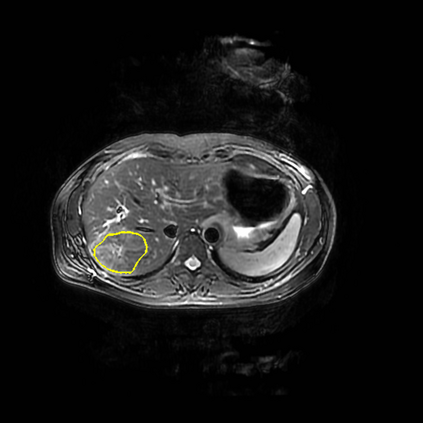

Radiomics uses quantitative medical imaging features to predict clinical outcomes. Currently, in a new clinical application, finding the optimal radiomics method out of the wide range of available options has to be done manually through a heuristic trial-and-error process. In this study we propose a framework for automatically optimizing the construction of radiomics workflows per application. To this end, we formulate radiomics as a modular workflow and include a large collection of common algorithms for each component. To optimize the workflow per application, we employ automated machine learning using a random search and ensembling. We evaluate our method in twelve different clinical applications, resulting in the following area under the curves: 1) liposarcoma (0.83); 2) desmoid-type fibromatosis (0.82); 3) primary liver tumors (0.80); 4) gastrointestinal stromal tumors (0.77); 5) colorectal liver metastases (0.61); 6) melanoma metastases (0.45); 7) hepatocellular carcinoma (0.75); 8) mesenteric fibrosis (0.80); 9) prostate cancer (0.72); 10) glioma (0.71); 11) Alzheimer's disease (0.87); and 12) head and neck cancer (0.84). We show that our framework has a competitive performance compared human experts, outperforms a radiomics baseline, and performs similar or superior to Bayesian optimization and more advanced ensemble approaches. Concluding, our method fully automatically optimizes the construction of radiomics workflows, thereby streamlining the search for radiomics biomarkers in new applications. To facilitate reproducibility and future research, we publicly release six datasets, the software implementation of our framework, and the code to reproduce this study.

翻译:放射科使用定量医学成像特征来预测临床结果。目前,在一个新的临床应用中,通过一个超常试验和高压过程,通过人工操作,从广泛的现有选项中找到最佳放射法。在本研究中,我们提议了一个框架,自动优化每个应用程序的放射工作流程的建设。为此,我们将放射作为模块工作流程,并包括每个部件的大量通用算法。为了优化每个应用程序的工作流程,我们使用随机搜索和聚合的自动机学习方法。我们用12种不同的临床应用来评估我们的方法,结果在曲线下应用的以下领域:1) 脂色瘤(0.83);2) 脱氧型纤维瘤(0.82);3 初级肝脏肿瘤(0.80);4 气肠肿瘤(0.77)、5 彩虹肝脏移植(0.61); 6 脑膜细胞变异常(0.45); 7) 肝细胞变异常(0.8) 脑纤维变异位(0.80); 9) 直径直线型癌症(0.74) 和头型癌症(0.77) 直径研究(10) 。